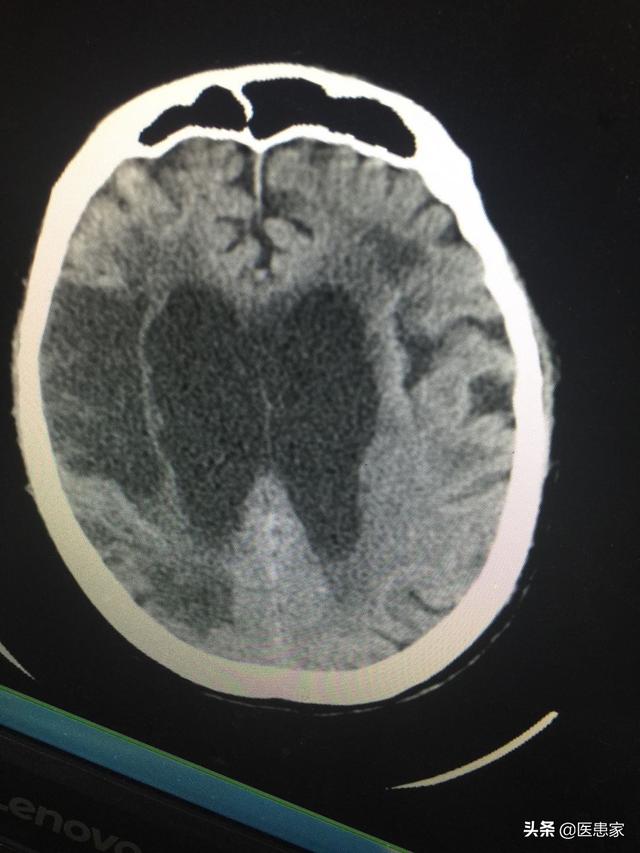

L'infarctus cérébral est causé par un flux sanguin artériel anormal dans certaines parties du cerveau, entraînant une hypoxie et des défauts dans les zones du cerveau insuffisamment irriguées, ce qui provoque des symptômes tels que le ramollissement et la nécrose du tissu cérébral, ainsi que des symptômes tels que l'aphasie et l'hémiparésie. Une étude connexe a montré que 24 à 48 heures après l'apparition de la maladie, des foyers de faible densité peuvent être observés dans la zone affectée au moyen d'une tomodensitométrie cérébrale. En outre, l'infarctus cérébral peut être détecté à temps grâce à l'IRM cérébrale. Les manifestations cliniques de l'infarctus cérébral sont les suivantes : vertiges, coma, aphasie, nausées, etc., qui s'accompagnent de complications, telles que l'hémorragie gastro-intestinale, la dépression post-cérébro-vasculaire, les infections pulmonaires et l'anxiété.

Le diagnostic d'infarctus cérébral peut être confirmé ou différencié sur la base des antécédents et des symptômes, combinés à la tomodensitométrie, à l'IRM et à la soustraction digitale.